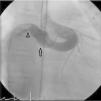

The patient was referred for a diagnostic cardiac catheterization. Angiography confirmed a coronary fistula measuring 13 mm in diameter at the aortic end and draining into the right atrium (RA) through at least two small openings (Figure 1). The left anterior descending (LAD) and circumflex (Cx) arteries originated in the proximal extremity of the fistula through two separate orifices. Catheterization showed normal right and left heart pressures, oxygen saturation step-up in the right atrium and Qp:Qs of 1.7. Informed consent was obtained and percutaneous closure of the fistula was attempted using a 16 mm Amplatzer® vascular plug II (AGA Medical). Through a femoral approach, a 7 Fr venous and a 6 Fr arterial sheath were used. A 6 Fr Concierge Amplatz Left 2 guiding catheter was positioned in the aorta at the fistula entrance and a 0.035 in Terumo® hydrophilic guide wire was advanced along the fistula, until the right atrium was reached. The wire was then snared and an arteriovenous (AV) loop was created. A 7 Fr Amplatzer Delivery System was used to deploy the device through the atrial end (Figure 2). A significant residual shunt was observed after deployment of the device. Cardiac enzymes were within normal range and the ECG showed no abnormalities. After this procedure anticoagulation was prescribed for six months and aspirin maintained thereafter.